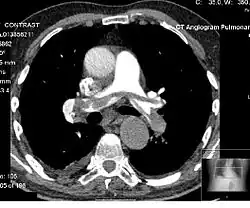

A single patient X-ray is not a computer generated image, even if digitized. However, in applications which involve CT scans a three-dimensional model is automatically produced from many single-slice x-rays, producing "computer generated image". Applications involving magnetic resonance imaging also bring together a number of "snapshots" (in this case via magnetic pulses) to produce a composite, internal image.

In modern medical applications, patient-specific models are constructed in 'computer assisted surgery'. For instance, in total knee replacement, the construction of a detailed patient-specific model can be used to carefully plan the surgery.[22] These three-dimensional models are usually extracted from multiple CT scans of the appropriate parts of the patient's own anatomy. Such models can also be used for planning aortic valve implantations, one of the common procedures for treating heart disease. Given that the shape, diameter, and position of the coronary openings can vary greatly from patient to patient, the extraction (from CT scans) of a model that closely resembles a patient's valve anatomy can be highly beneficial in planning the procedure.[23]